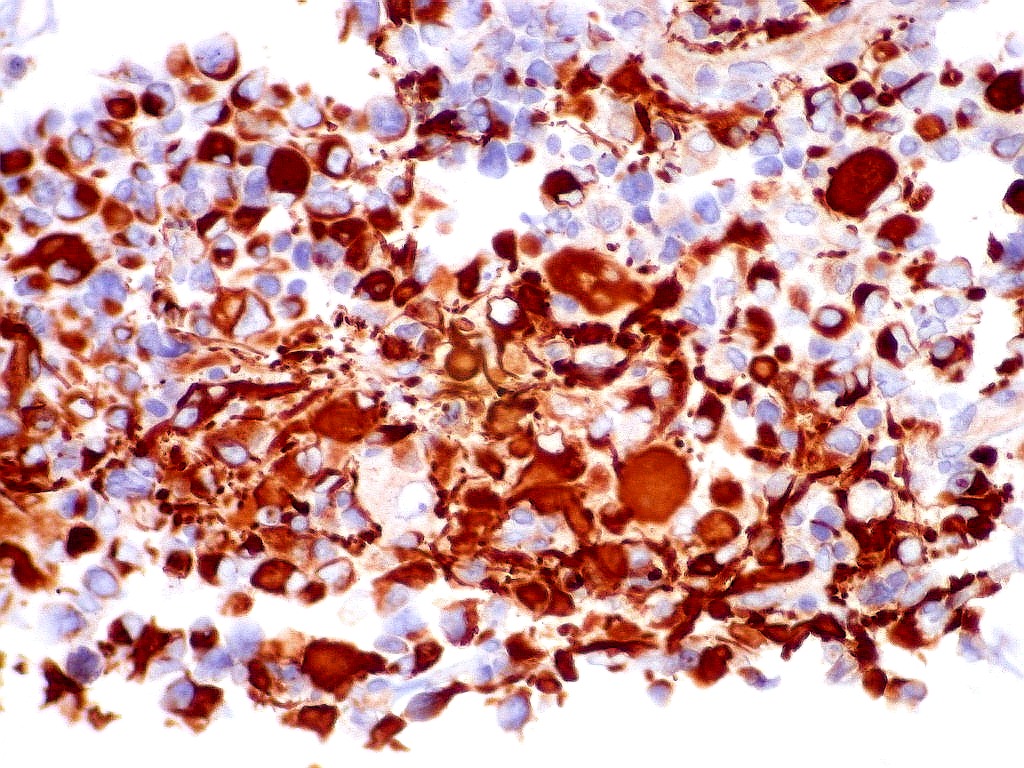

| EMA. Antígeno epitelial de membrana. Ocorre em epitélios, e também em células meningoteliais. Aqui fortemente positiva nas células deste tumor teratóide rabdóide atípico. Negativo no folículo linfóide incluído fortuitamente na amostra. Positivo também no epêndima do III ventrículo adjacente ao tumor. Notar que as células ependimárias são ciliadas. |